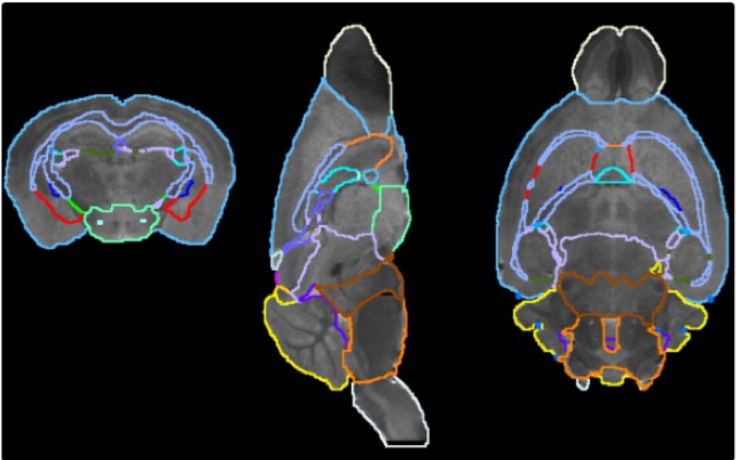

pmod’s tools provide comprehensive workflows for post-processing and quantification of imaging data for fundamental oncology research, development of radiotracers and theranostics, and in clinical research studies. Imaging scientists can trust pmod to reproducibly read their data, interpret the meta-data/units and help users calculate statistics such as SUV for their studies and publications.

Handle multimodality data and applications

• Multimodality segmentation tools – comprehensive semi-automated and manual tools for precision and reproducibility